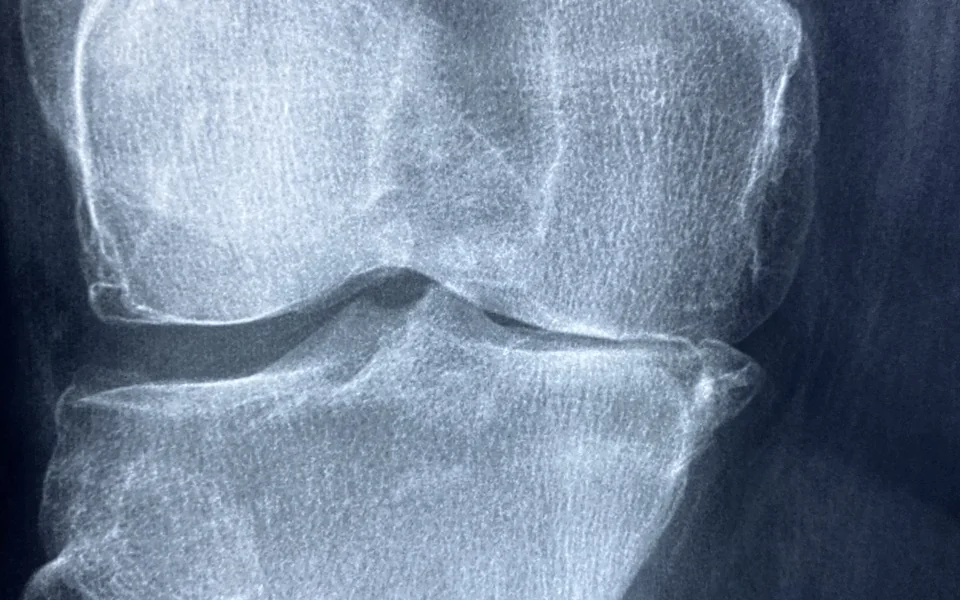

• 관절 및 근육 통증: 뻣뻣함 또는 만성적인 불편감이 나타납니다.